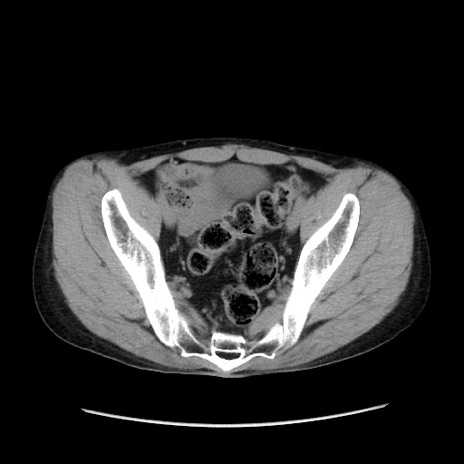

症例37(横断像)

【症例】40歳代 男性

【主訴】腹痛

【現病歴】4時間ほど前に電車に乗車中に臍部上より腹痛出現。徐々に増悪し起立困難となり、救急外来受診。生ものは数日食べていない。今朝お雑煮を食べた。

【身体所見】BT 36.8℃、BP 117/84mmHg、HR 91/min、SpO2 97%、苦悶様、腹部:臍上部広範囲圧痛あり、反跳痛±

【データ】WBC 8100、CRP 0.03